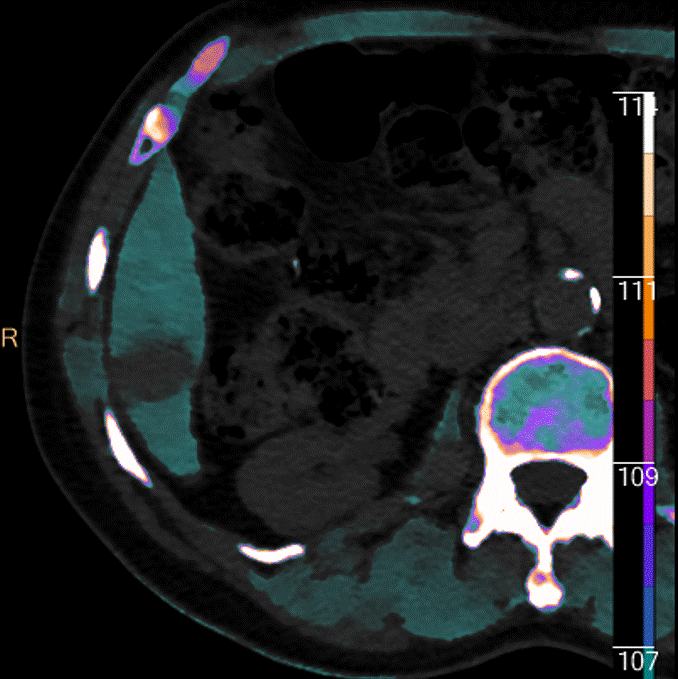

Arterial phase, iodine map.

But wait, there is more. There is a subtle additional focus on arterial enhancement in segment 4A. This simply cannot be seen on conventional images, but cannot be missed on 40 keV image and iodine map. On the delayed scan, this lesion shows up much better on the electron density map.

Arterial phase, 40 keV image. See the 2 dots of enhancement?